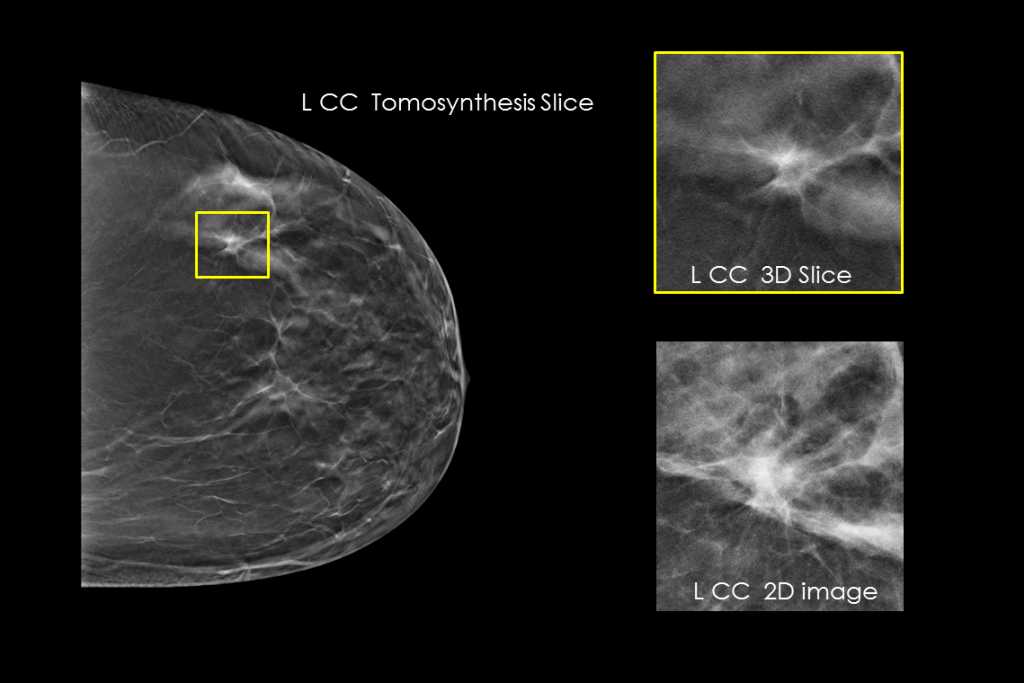

Immagini cliniche di una mammografia

Immagini cliniche di una mammografia con lesione sospetta